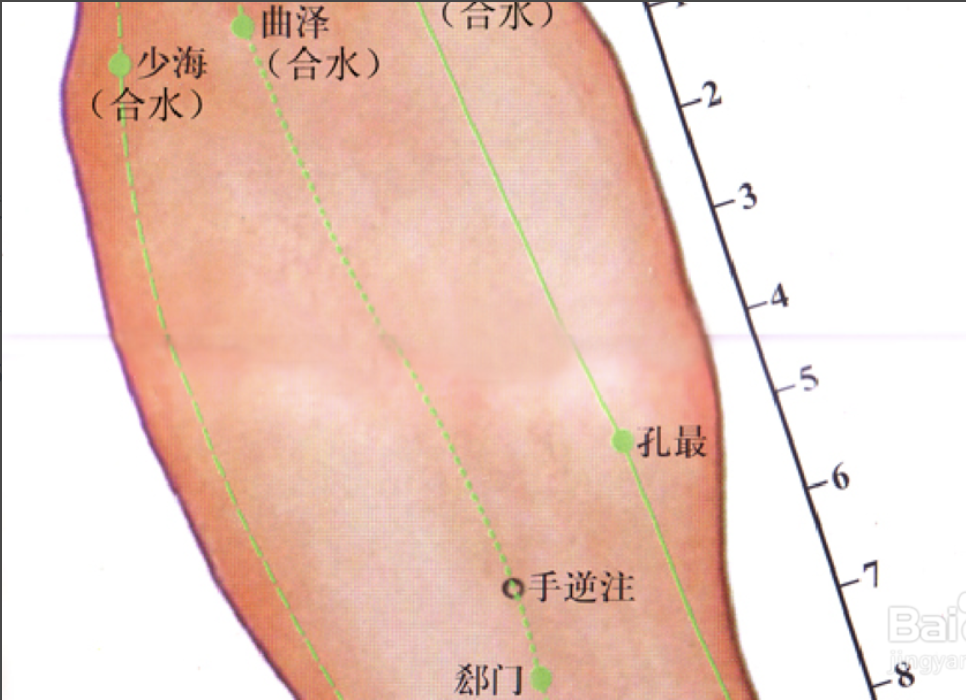

曲泽

【定位】 在肘横纹中,当肱二头肌腱的尺侧缘(图 10-27-2)。

郗(xī)门

【定位】 在前臂掌侧,当曲泽与大陵的连线上,腕横纹上 5 寸。

间使

【定位】 在前臂掌侧,当曲泽与大陵的连线上,腕横纹上 3 寸,掌长肌腱与桡侧腕屈肌腱之间。